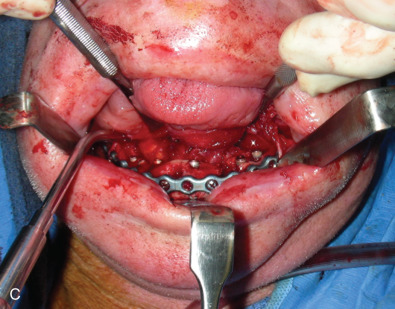

The evolution of mandibular fracture complications – infection, delayed union, malunion, nonunion, malocclusion, TMJ disorders, paresthesia, etc. – along with causes – the injury itself, inadequate or inappropriate treatment, patient compromise, misadventure, etc. – are described. Contemporary management is outlined with a series of illustrative examples. An underlying theme is that the treatment of failed rigid fixation, the standard of care today, is a bigger plate and more screws.

All of these systems allowed for convalescent function – life without MMF. RIF had the potential of dramatically shortening the course of treatment. However, its use was highly technique-sensitive with a steep learning curve. Thus, the incidence of complications increased dramatically due to operator error. Complications related to inadequate reduction – “the OIF” (open internal fixation … without the reduction) ( Figs. 1.16.1–1.16.3 ), inadequate fixation ( Figs. 1.16.4–1.16.7 ) and surgical misadventure ( Fig. 1.16.8 ) began to appear. Indeed, by the early 1990s operator error was the number one cause of mandibular fracture complications. Quite obviously, RIF is very unforgiving. When done poorly, one has a rigidly fixed mistake. The latest series of misadventures are related to the use of IMF screws. Bone-anchored arch bars will most likely be next. Not all believe that RIF and convalescent function is cost-effective with respect to the increased cost, potential for complications, and patient acceptance.